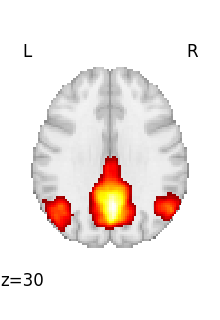

first_rsn is a 3D image.

We can then plot it

<nilearn.plotting.displays._slicers.OrthoSlicer object at 0x7f3bc7cf1610>